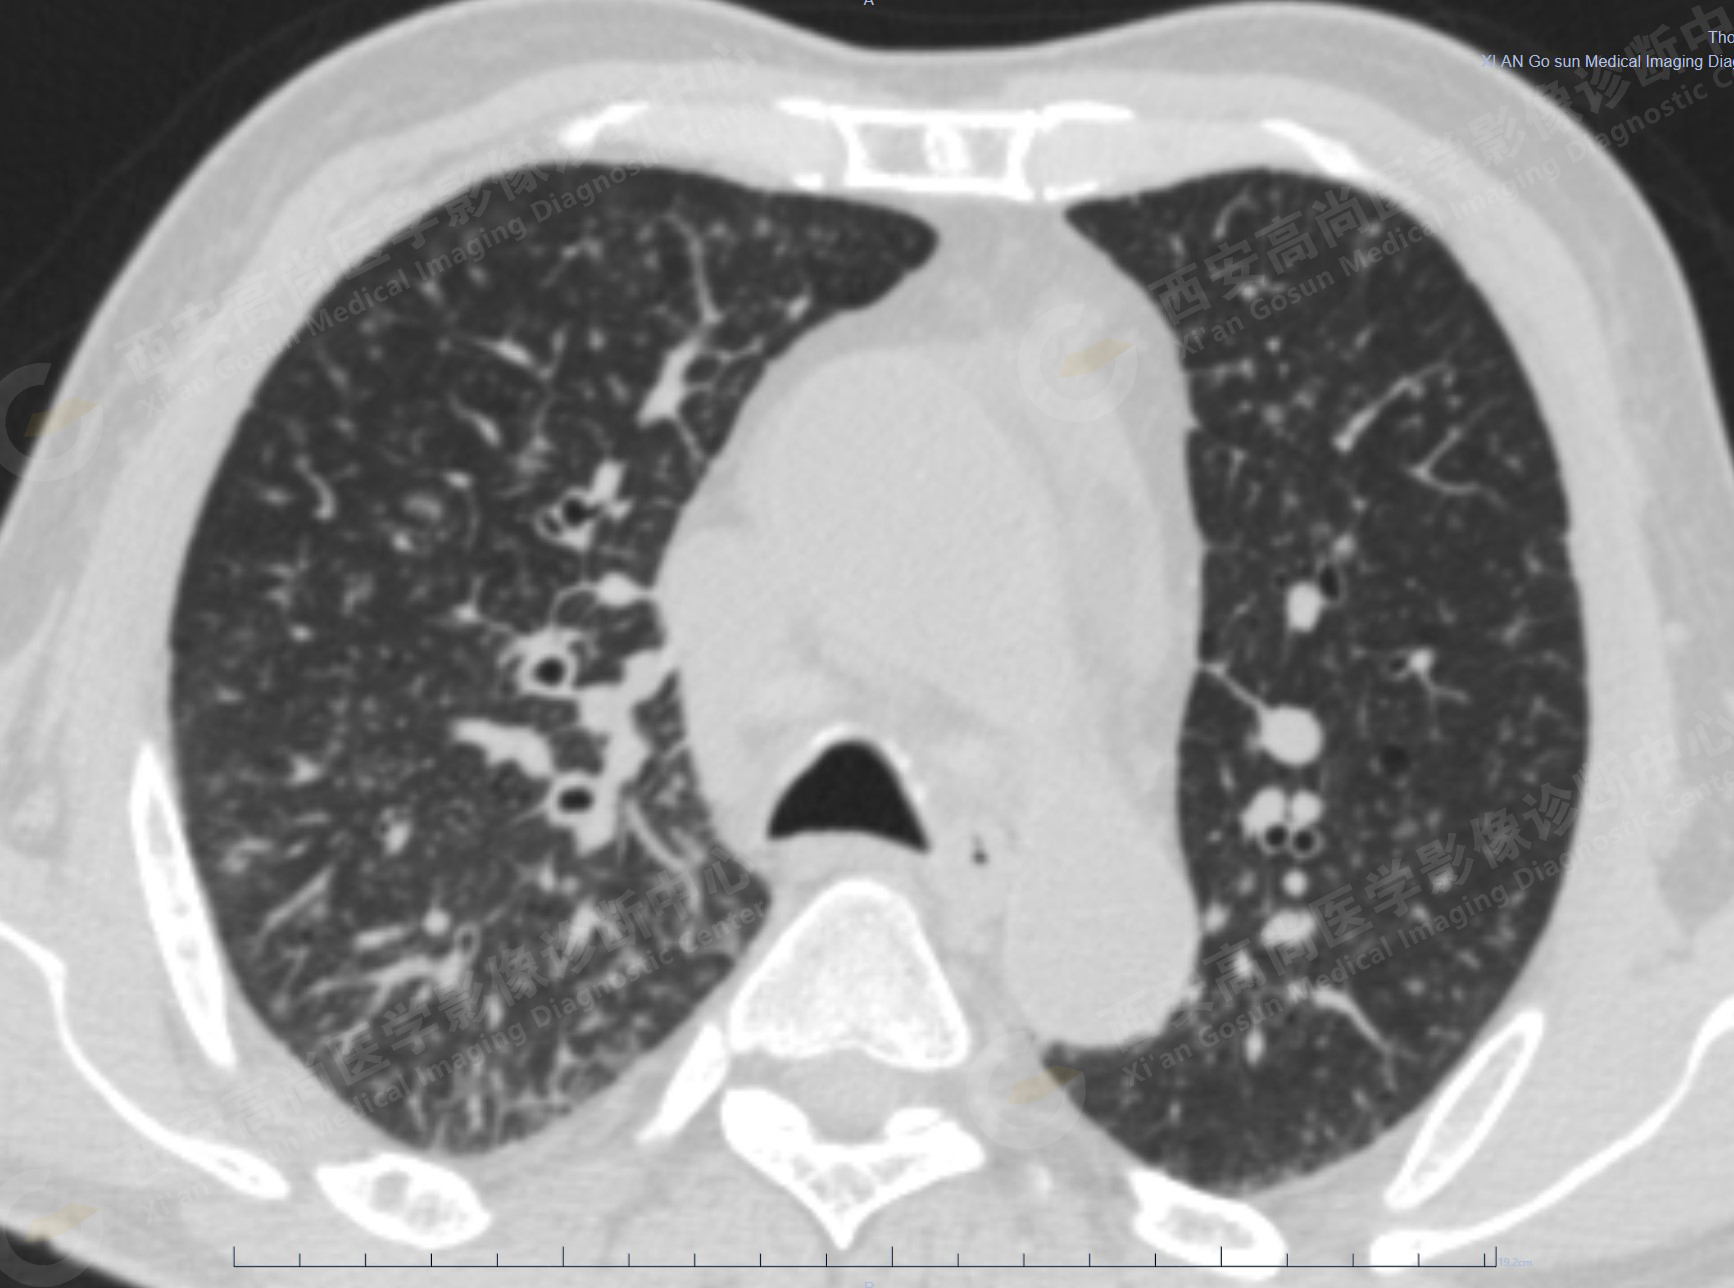

病史:男性,61歲,咳嗽1月余,CT發(fā)現(xiàn)肺結節(jié)。外院腋窩淋巴結穿刺活檢提示:轉移性腺癌。行PET/CT進行腫瘤分期。

1.以下為肺內(nèi)原發(fā)灶

1.右肺中葉內(nèi)側段軟組織結節(jié),呈淺分葉狀,邊緣可見毛刺及胸膜牽拉征,呈FDG代謝異常增高,考慮為周圍型肺癌。

2.雙肺內(nèi)彌漫性分布大小不等實性小結節(jié)灶及粟粒狀高密度影,均未見FDG代謝明顯異常增高,均多考慮為癌性淋巴結炎及轉移性病變。